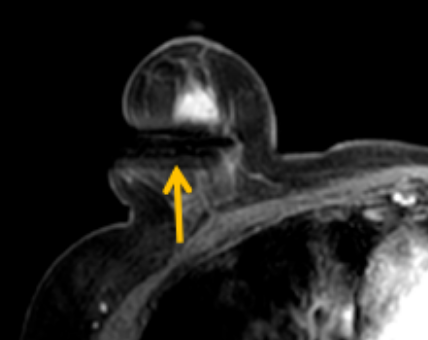

陳寶瑩評估圖像后發(fā)現(xiàn)病變?yōu)閮H僅在磁共振增強(qiáng)時顯示,為非腫塊樣病變,比較散,必須取得足夠多的組織才能確保病理檢查的準(zhǔn)確性,常用的核芯針活檢獲取的組織較少,因此最終確定了磁共振引導(dǎo)下行真空輔助抽吸旋切活檢。取得患者及家屬認(rèn)可后,陳寶瑩帶領(lǐng)團(tuán)隊(duì)開始進(jìn)行術(shù)前準(zhǔn)備。

針對患者乳房小固定難度大這一問題,陳寶瑩通過巧妙體位和固定器的調(diào)整,順利固定好乳房。經(jīng)過磁共振多模態(tài)掃描,陳寶瑩找出病變活性成分相對集中區(qū)域,精準(zhǔn)確定穿刺路徑,置入引導(dǎo)針、旋切針,到位后多角度旋切取出足量組織,拔除旋切針后即時行磁共振掃描,精準(zhǔn)取得組織且術(shù)區(qū)出血很少,遂加壓包扎,整個過程非常順利,旋切活檢后患者回家休息。兩天后隨訪,李女士沒有任何不適,五天后皮膚上幾毫米的小切口已經(jīng)愈合。最終病理結(jié)果證實(shí)為乳腺導(dǎo)管原位癌,為早期乳腺癌,為患者后續(xù)針對性治療奠定了基礎(chǔ)。